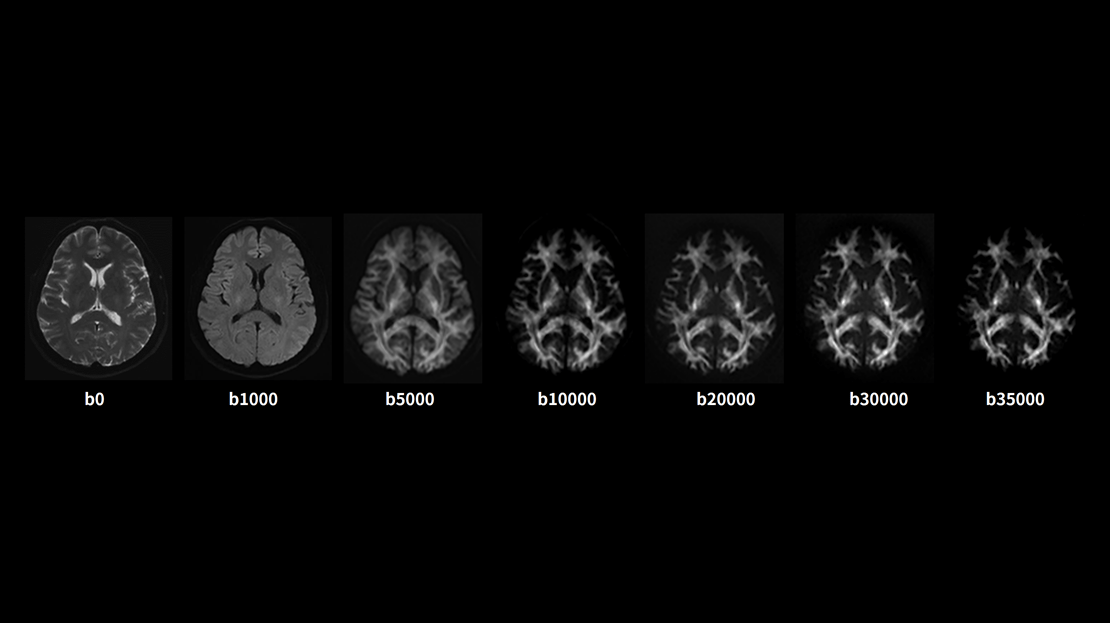

高分辨DTI